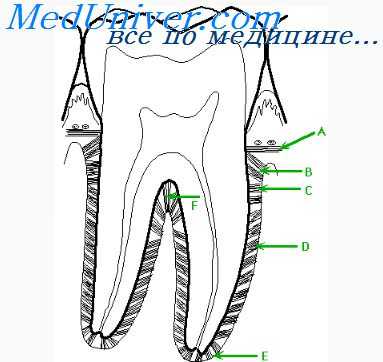

Пародонтальный карман — это главный дифференциальный признак пародонтита, который позволяет отличать его от предшествующего хронического гингивита.

Клинически формирование пародонтального кармана начинается с углубления зубодесневой борозды, перемещения эпителиального прикрепления к зубу с области эмалево-цементной границы на цемент. Решающими факторами для начала формирования ПК являются изъязвление эпителиального слоя в области прикрепления, внутритканевое проникновение пародонтопатогенной микрофлоры и образование несозревающей грануляционной ткани, обладающей литической активностью и, в свою очередь, усиливающей деструкцию соединительнотканной основы под эпителиальным дефектом. Последующее углубление управляется активированными остеокластами (под влиянием цитокинов и ФНО), простагландинами и металлопротеиназами на фоне подавления активности остеобластов.

Причины появления пародонтального кармана

Зуб соединен с челюстной костью с помощью специальной связки — периодонта. Периодонт необходим для амортизации зуба и равномерном распределении жевательной нагрузки. В здоровом состоянии периодонт герметично защищен от проникновения патогенных бактерий зубоэпителиальным соединением. Между десной и зубом образуется десневой желобок. Если происходит разгерметизация периодонта, на прикорневой части зуба начинает скапливаться бактериальный налет, который провоцирует формирование зубного камня со временем.

Если патологический процесс не остановить, он начинает поражать костную ткань челюсти. В результате воспаления появляется пародонтальный карман — от десны до пришеечной части зуба. Глубина кармана характеризуется степенью выраженности патологии. В номе величина углубления десны не должна превышать 3 мм. Если десна «оседает» вниз, это говорит о развивающемся патологическом процессе.